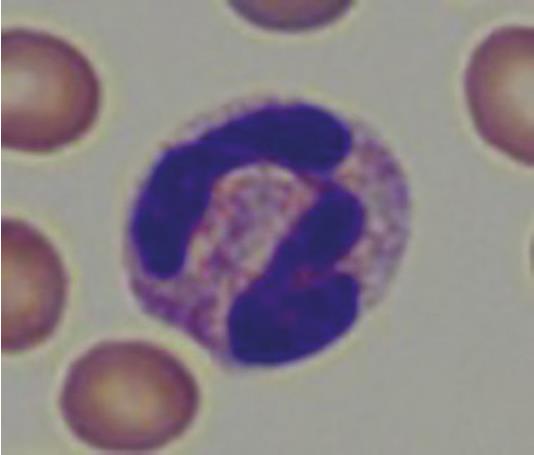

Neutrophil granulocytes in guinea pigs are also referred to as “pseudo-eosinophils” (Fig. 4) due to their acidophilic staining. These can easily be confused with eosinophil granulocytes, but are smaller in comparison, as their nucleus is less segmented and contains smaller granules.

- Fig. 4: “Pseudo-eosinophil”